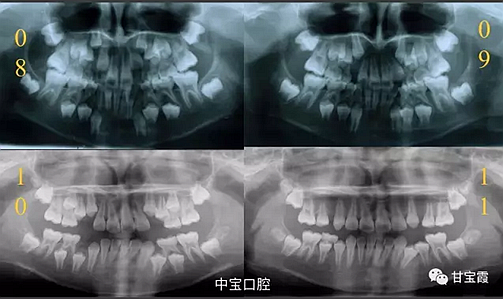

經(jīng)過我臨床檢查和X線的診斷,決定早期干預(yù),每三個月定期復(fù)診檢查一次,并拔掉了幾個乳牙和四個恒牙,正畸專業(yè)叫序列拔牙。

經(jīng)過三年零九個月的看護,最終戴上了固定矯治器,但是大家不難發(fā)現(xiàn),孩子的牙齒已經(jīng)排齊,上下中線也基本對齊,面型也好看多了,這樣矯正就變得簡單,療程自然縮短,孩子也不遭罪了。

這個故事告訴我們,只有家長早點把孩子帶給正畸醫(yī)生檢查,才能早期發(fā)現(xiàn)早期治療。起到了事半功倍的效果。矯正以后還不容易復(fù)發(fā),因為從08年的初診到11年戴矯正器這三年多的時間里,孩子的牙齒是自己長好的。